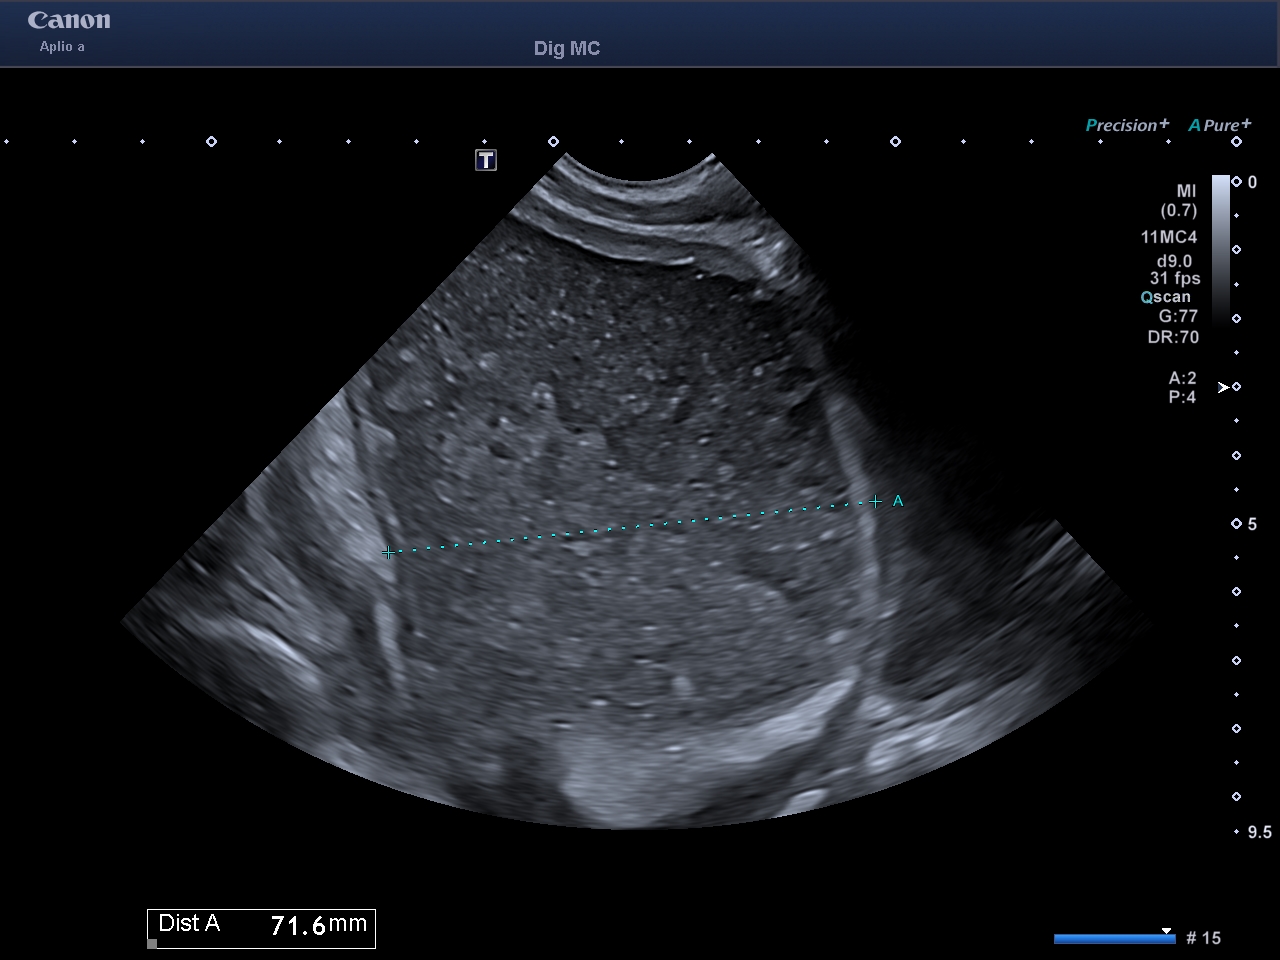

L'occlusion du grêle est très facile à voir en échographie

C'est la seule technique radiologique qui montre la motricité intestinale en temps réel

On peut voir en cas d'occlusion: